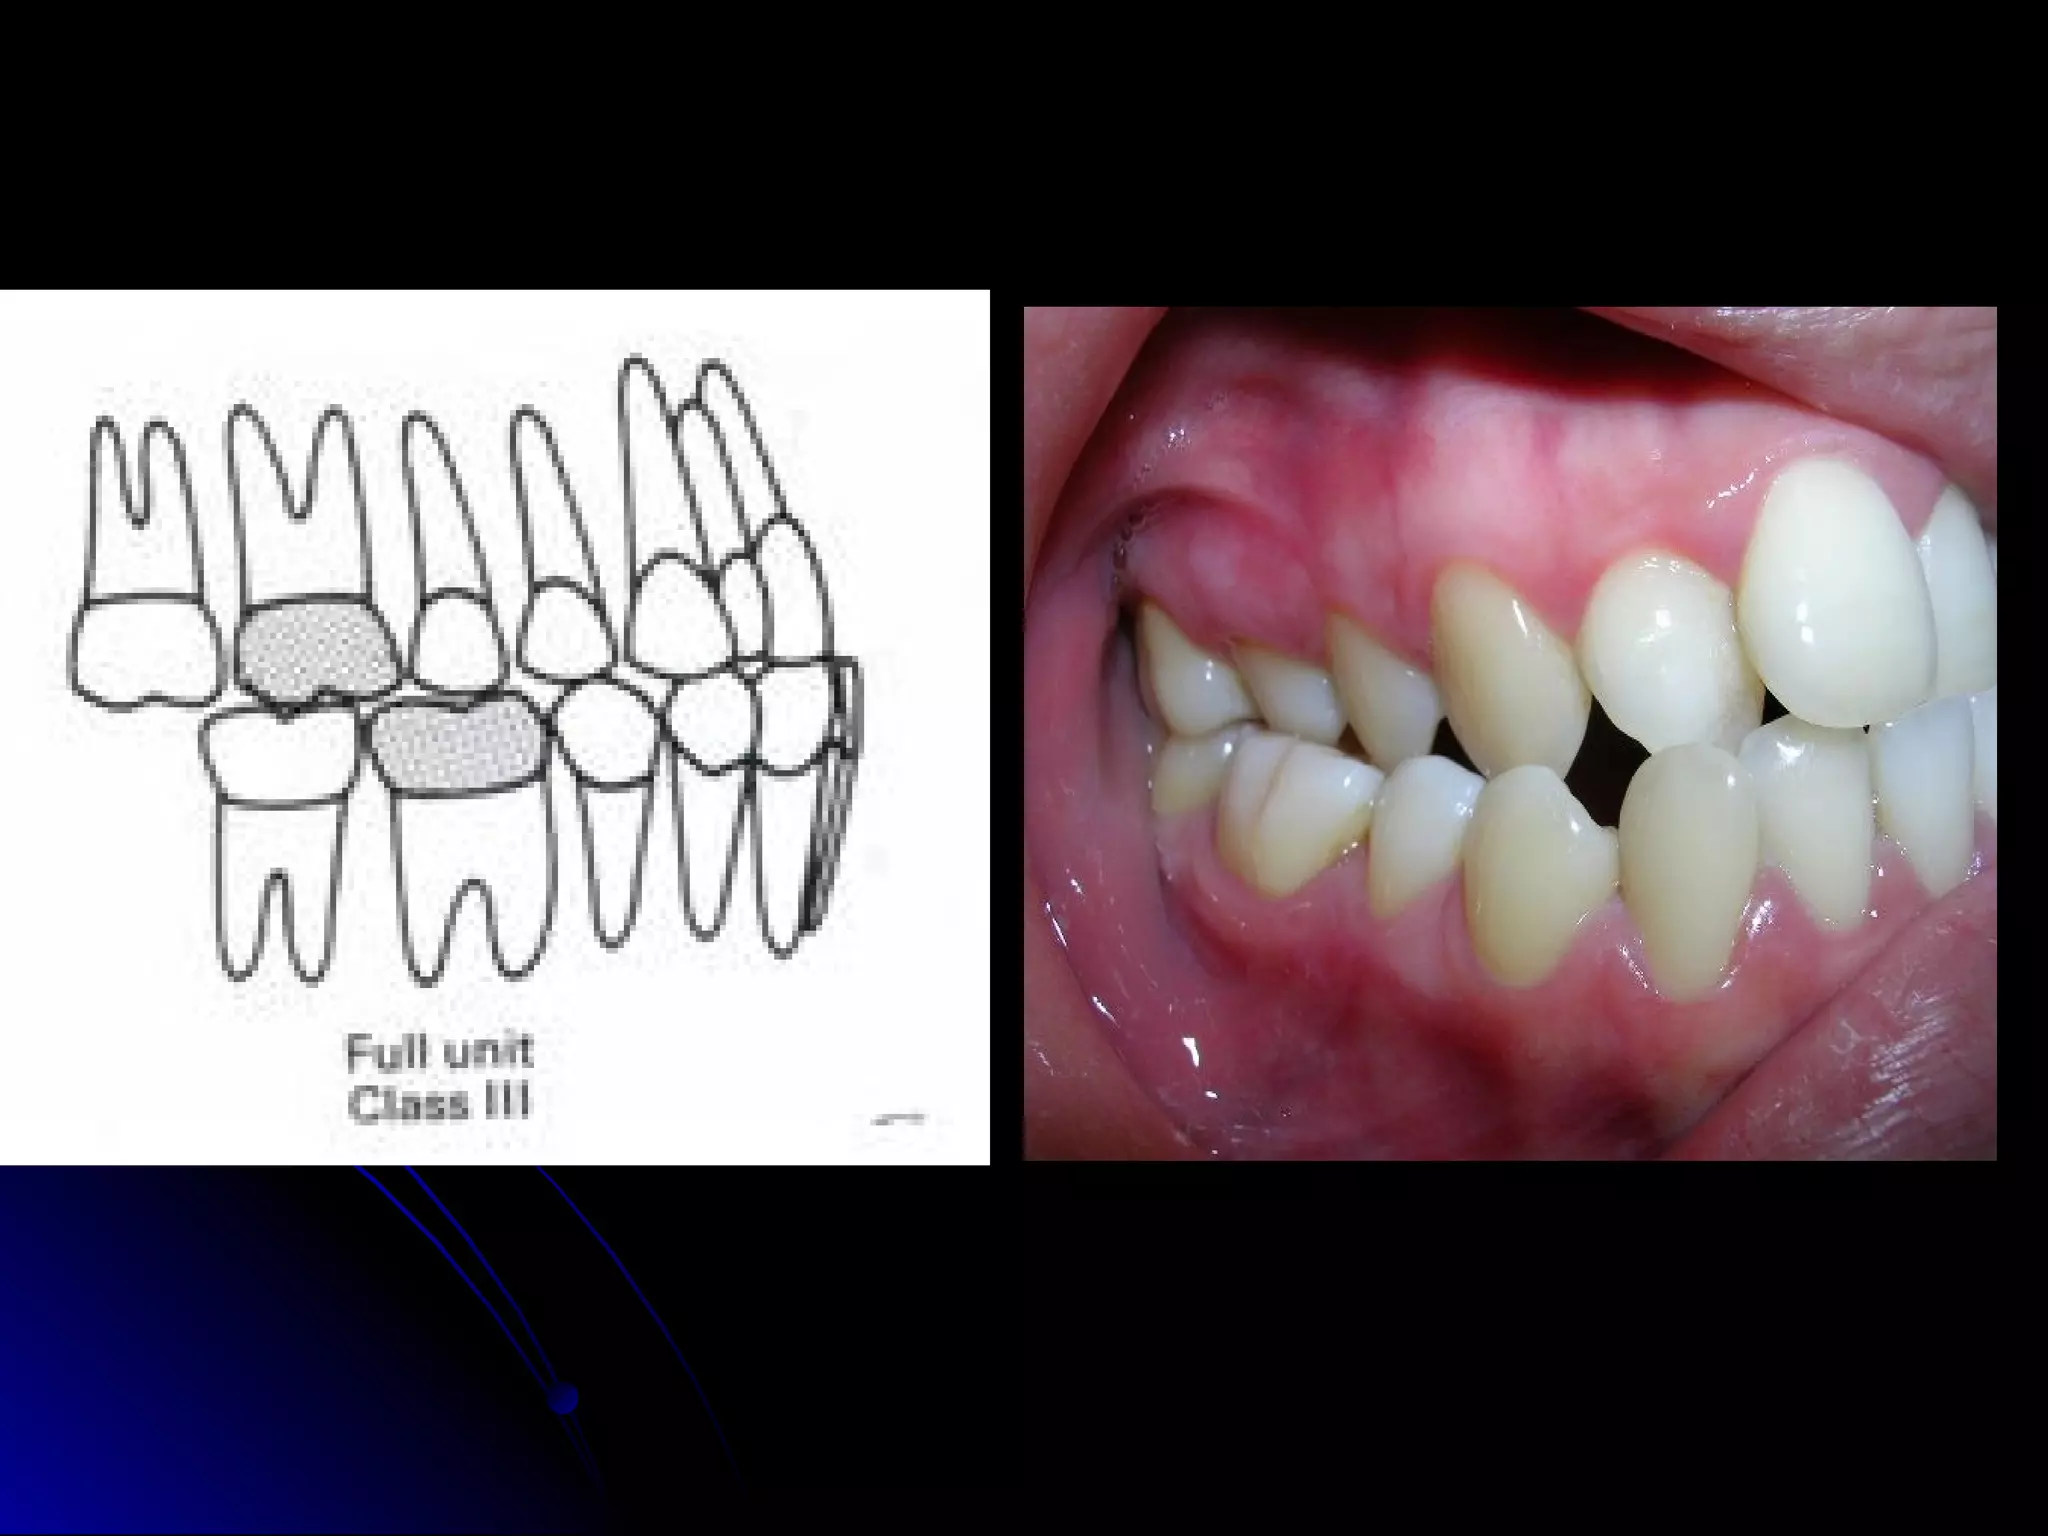

CLASS III MALOCCLUSION.

The upper first permanent molar occludes distal to the

buccal developmental groove of the lower first permanent

molar.

Line of occlusion not specified.

CLASS III MALOCCLUSION. Theupper first permanent molar occludes distal to the buccal developmental groove of the lower first permanent molar. Line of occlusion not specified.